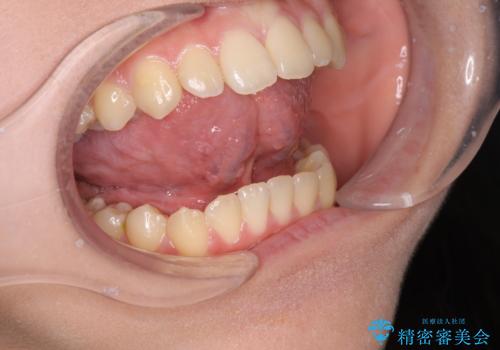

舌が短く話しづらい、滑舌を改善する小手術

- 「舌が短く話しづらい、サ行が発音しづらいので改善したい。」と希望され来院されました。

舌の動きを改善し、発音しやすくなるよう即日の小手術を計画します。